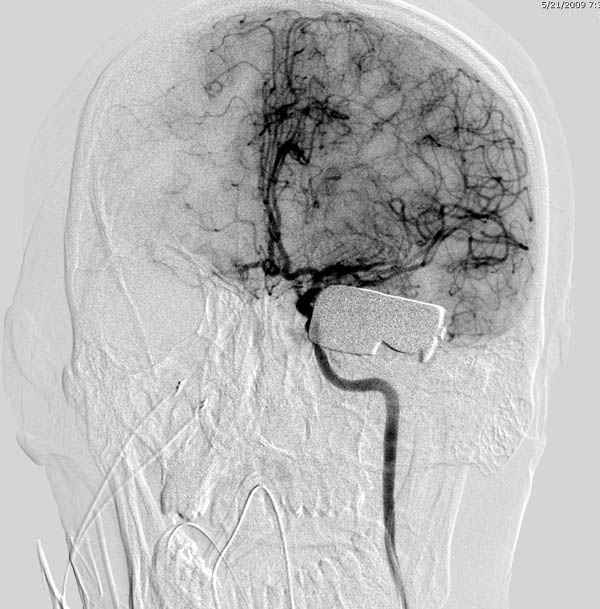

По протоколу сделаны все необходимые исследования: рентген, ангиограмма с 3Д реконструкцией, где обнаружили что все жизненно важные сосуды не задеты, даже некоторые "сидят" изгибаясь на ноже.